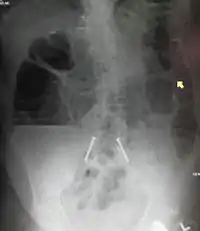

![]() يوضح التصوير بأشعة إكس على البطن وجود انسداد بالأمعاء الدقيقة والمريض في وضع الوقوف.لاحظ وجود مستويات متعددة من السوائل والغازات. يوضح التصوير بأشعة إكس على البطن وجود انسداد بالأمعاء الدقيقة والمريض في وضع الوقوف.لاحظ وجود مستويات متعددة من السوائل والغازات. | |

من ضمن الأشياء التي يكشف عنها التصوير الإشعاعي وجود انتفاخ بالأمعاء ووجود مستويات متعددة (أكثر من ستة مستويات) من السوائل والغازات في صور الأشعة التي تؤخذ على البطن والمريض في وضع الاستلقاء على الظهر تارة والوقوف تارة أخرى.

وعلاوةً على ذلك، فمن الممكن استخدام حقنة الباريوم الشرجية أو صور أشعة ملونة للأمعاء الدقيقة أو الأشعة المقطعية لتحديد درجة انسداد الأمعاء، وما إذا كان الانسداد جزئيًا أم كليًا، وكذلك لمعرفة سبب الانسداد.